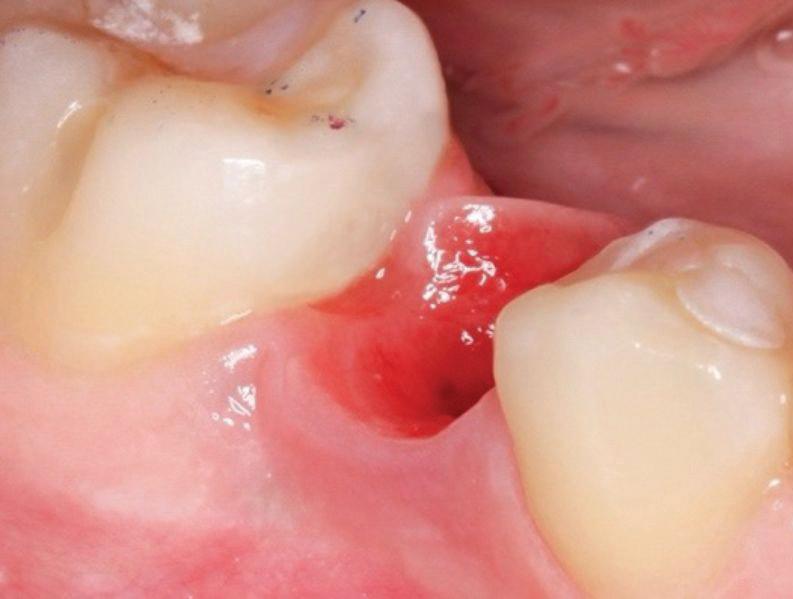

Clear radiographs are essential to accurate diagnosis and are a special test that dentists per form regularly many times throughout the day. Following the ALARA principle, we want to ensure we take a minimal number of radio graphs to ensure low radiation dosage so to repeat radiographs due to operator error should be avoided. The use of film holders allow the clinician to visualise how the radiographs should be taken to optimise the clarity of the image and ensure the diagnostic value of the image. Hawe Solutions x-ray film holders...

• Allow exact posi tioning of the film or phosphor plate relative to the tooth - no bending and thus no distortion;

• Require no guesswork - exclusive, automatic reliance on the extraoral aiming and centring device;

• Deliver semi-reproducible images (quasi standardisation)the use of film holders allows some sense of reproducibility for assessment over time; and

• Produce optimally clear radiographs.